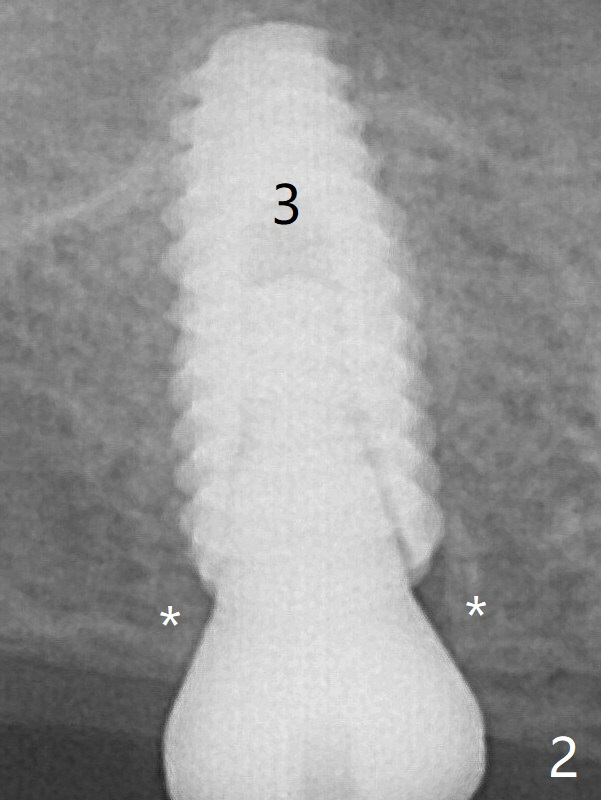

A 4.5x10 mm implant is placed at #3 subcrestal; the healing abutment is incompletely seated (Fig.2). One month postop, the implant is infected with distal bone loss (Fig.4). Bone graft is added. Bone loss seems to reduce 4 months post implant placement (Fig.6 *). Uncover is conducted at the site of #3; there is no superficial infection 7.5 months postop (Fig.8). There is a large buccal defect upon incision with dark hemorrhage. In fact the bone density is low crestally (Fig.8 *). Bone graft is placed for the 2nd time. Eleven months later (1.5 years post implant placement), the bone regrows crestal (Fig.9 *). 保险:愈合螺帽